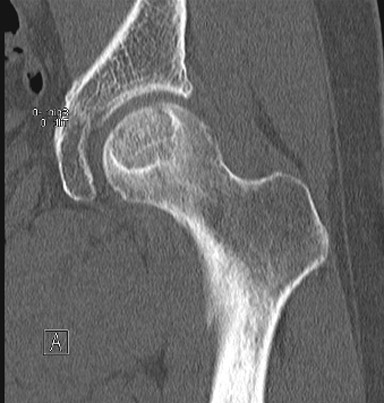

Мы применяем Bone Marrow Aspirate для Pre-collapse состояний. Метод включает аспирацию костного мозга из крыла, центрифугирование, и после разделения на фракции - иньекция через 3 мм инструментом, разработанным компанией BioCUE BIOMET Biologics. Treatment of osteonecrosis with autologous bone marrow grafting. Hernigou P, Beaujean F.

До и через год после лечения.